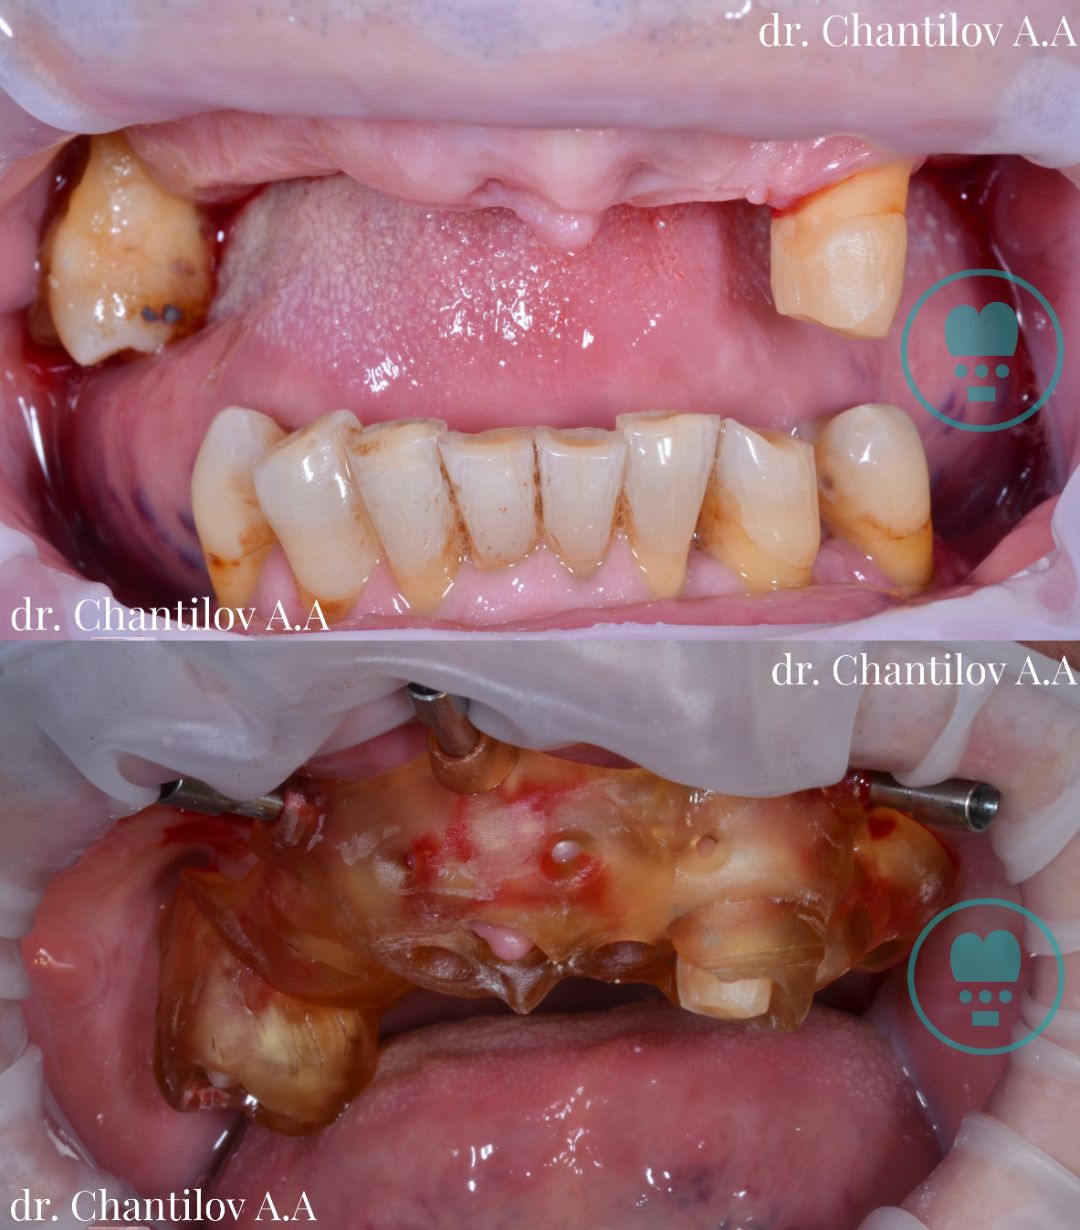

Имплантация зубов челюсти - фото до и после

Изготовление индивидуального шаблона